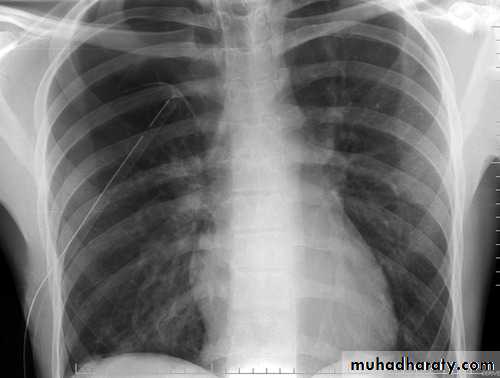

Hemothorax

Fall from the 2nd floor